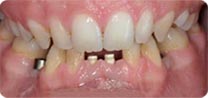

安卓健临床案例分享

安卓健种植产品销往全球100多个国家精密工程CFDA

权威认证,可放心使用。安卓健种植体手术程序简单,

更少创伤,更快恢复,更加安心。